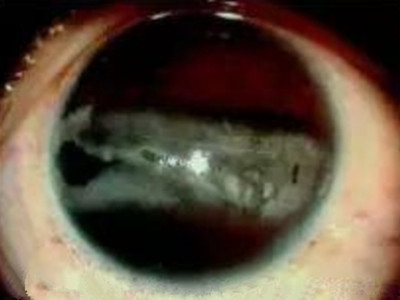

带状角膜病变瞳孔两侧发白图

带状角膜病变症状较轻时,表现为瞳孔两侧出现形状不规则的灰白色钙质沉着,多为单眼发病。本病进展缓慢,初期症状较轻,不易发现,但晚期会有明显的视力减退。